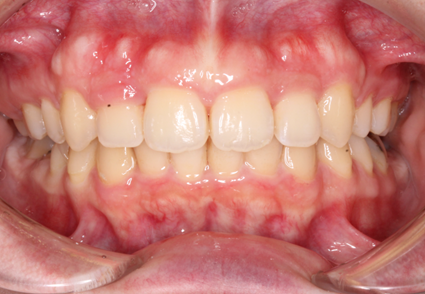

マウスピース矯正は、専用の透明なマウスピースを使用する矯正方法です。この方法の最大の特長は、装置が目立たないことです。透明な素材で作られているため、装着していてもほとんど見えず、日常生活で他人に矯正をしていることを気づかれる心配がありません。見た目を気にせず、自然な笑顔を保ちながら治療が進められます。

さらに、マウスピースは、必要に応じて簡単に取り外すことができます。食事の際にはマウスピースを外して好きなものを自由に楽しむことができ、矯正中の食生活に制限がかかる心配がありません。また、歯磨きやマウスピースの洗浄も簡単に行えるため、口腔内を清潔に保ちやすく、虫歯や歯周病のリスクを減らすことができます。

マウスピースは、患者さん一人ひとりの歯並びに合わせてカスタマイズされており、快適な装着感を提供します。治療は、段階的に新しいマウスピースを使用して歯を少しずつ移動させるので、痛みも比較的少ないです。